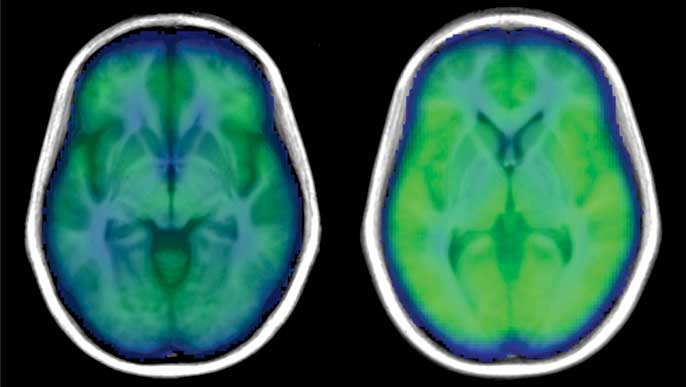

In the study, published Aug. 28 in the peer-reviewed journal PLOS ONE, researchers measured blood flow in the brain using a non-invasive MRI procedure: the global blood volume and oxygen dependent (BOLD) signal. This method is usually used to observe brain activity. Because previous research showed that poor regulation of blood in the brain might be a problem for people with sleep apnea, the researchers used the whole-brain BOLD signal to look at blood flow in individuals with and without obstructive sleep apnea (OSA).

“When we looked at the results, we didn’t see much difference between the participants with and without OSA in the Valsalva maneuver,” said Macey. “But for the hand-grip and cold-pressor challenges, people with OSA saw a much weaker brain blood flow response.”

The researchers believe that the reason there were differences in the sleep apnea patients during the hand-grip and cold pressor challenge was because the signals from the nerves in the arms and legs had to be processed through the high brain areas controlling sensation and muscle movement, which was slower due to the brain injury. On the other hand, the changes from the Valsalva are mainly driven by blood pressure signaling in the chest, and do not need the sensory or muscle-controlling parts of the brain.